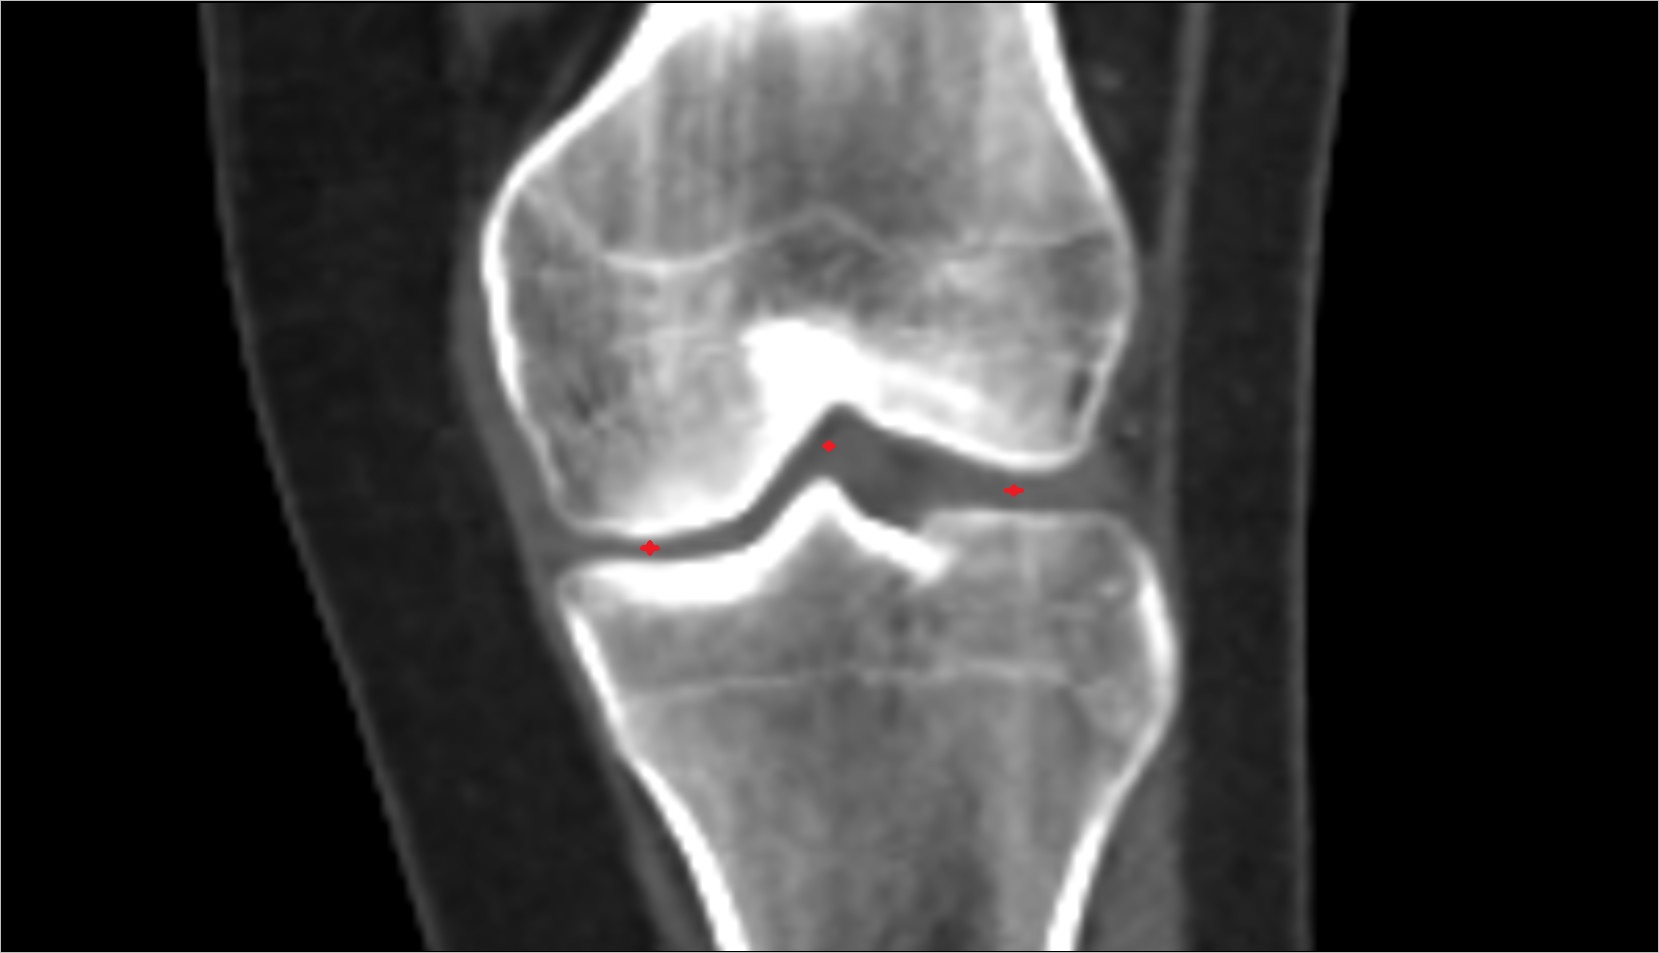

- Knee Joint

- Medial meniscus

- Lateral meniscus

- Medial collateral ligament

- Lateral collateral ligament

- Anterior cruciate ligament

- Posterior cruciate ligament